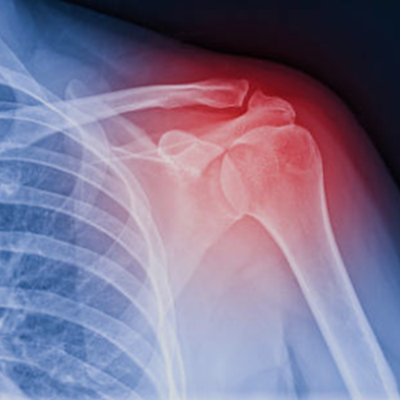

회전근개 증후군 (M75.1) 전문가와 함께하세요.

회전근개 증후군 (질병산재) 신청은 일반 사고로 인한 산재 신청보다 업무 연관성을 명확히 입증해야 하는 까다로운 과정이 포함됩니다. 저희는 수많은 사례를 처리한 경험과 법률적 지식을 바탕으로, 근로자가 불이익을 받지 않도록 철저하게 대응합니다.

회전근개 질환으로 고통받고 있다면 상담 받아보세요.